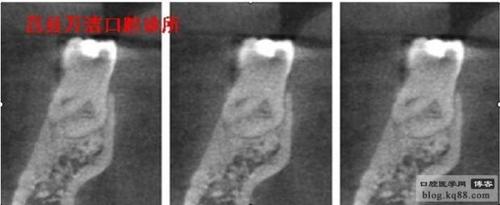

[转载]揭秘下颌第一磨牙远舌根/莒县-牙医

三)牙根的凹陷 在牙根的两侧各有一条凹陷,与舌隆突相衔接